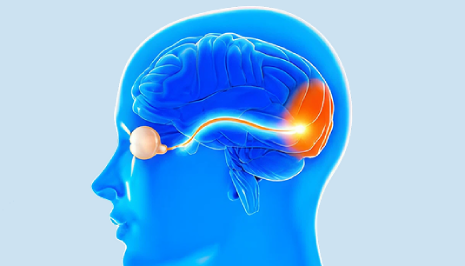

Squint Eye Treatment

What is Squint Eye? Squint eye or strabismus is one of the neurological visual disorders whereby the normal neur

Neuro-Ophthalmology

Neuro-ophthalmology focuses on vision problems caused by disorders of the brain, optic nerves, and eye movement pathways.